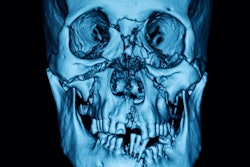

For alveolar bone graft planning, use CT with multiplanar reconstructions (MPR) and surface volumetric (3D), the authors recommended. For planar measurements, axial and coronal CT scans and volumetric measurements before bone grafting give a more accurate picture and help with surgical planning.

"Three-dimensional CT data is especially helpful in evaluating patients with severe craniofacial asymmetry, because they do not suffer from the magnification and distortion-related problems inherent in 2D projections," the authors wrote.

Same 8-year-old girl. Planar measurement (axial) and volumetric measurement after the alveolar bone graft (volume: 0.72cc3).When evaluating bone grafts with 3D CT, bone loss is more prominent in the bucco-palatine direction, and if resorption is higher than 50% or there is lack of normal eruption of adjacent teeth, graft failure should be suspected, according to Gómez-Chiari. Facial symmetry can be assessed by measuring the height from the pyriform aperture to the apex of the upper incisor in a coronal plane.